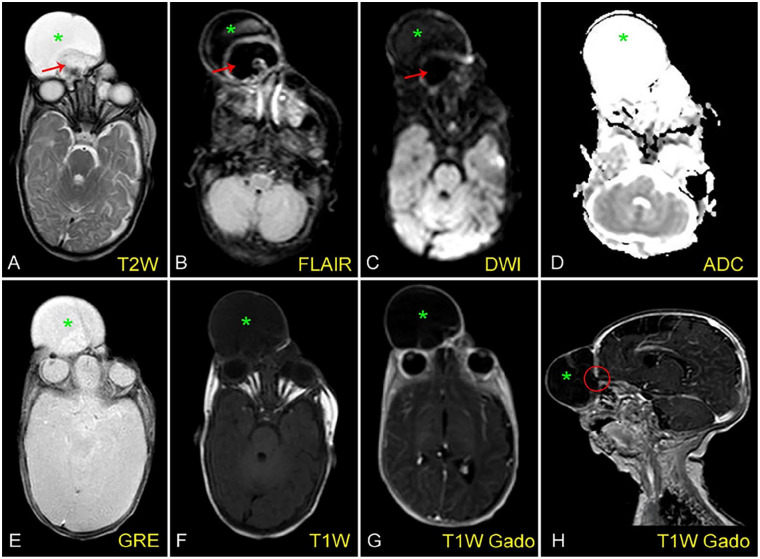

脑膜囊肿是头颅囊肿的一种罕见亚型,可表现为不同位置和不同特征。另一方面,泪囊也是一种罕见的解剖学疾病,通常表现为位于鼻子和眼睛之间的囊肿。一般来说,区分这两种病变并不困难。本病例中,一名胎儿疑似患有泪囊炎,产后最终被诊断为脑膜囊肿,凸显了区分这两种病症的复杂性。文章详细介绍了患者的产前检查、影像学检查结果以及随后的手术干预,强调了细致诊断对有效产前管理的重要性。该病例揭示了与不典型头畸形相关的潜在疏忽和误诊难题,为从事产前诊断和管理的临床医生提供了宝贵的见解。

Meningocele, a rare subtype of cephalocele, can manifest in various positions and exhibit diverse characteristics. On the other hand, dacryocystocele, also a rare anatomical disorder, typically presents as a cyst located between the nose and the eye. Generally, distinguishing between these 2 lesions is not difficult. The presented case involves a fetus with suspected dacryocystocele, ultimately diagnosed postpartum as meningocele, underscoring the complexities in distinguishing between these conditions. The article details the patient's prenatal examinations, imaging findings, and the subsequent surgical intervention, highlighting the significance of meticulous diagnosis for effective prenatal management. The case illuminates the potential oversight and misdiagnosis challenges associated with atypical cephaloceles, contributing valuable insights for clinicians involved in prenatal diagnosis and management.